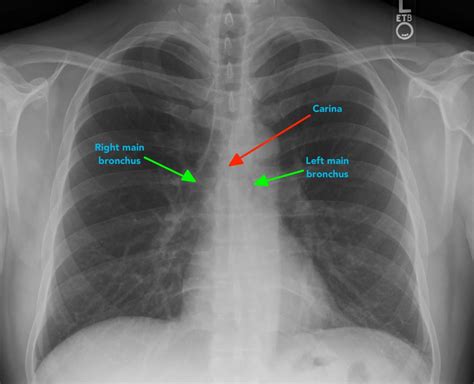

A bronchitis X ray is a crucial diagnostic tool that helps healthcare providers visualize the lungs and bronchial tubes. This imaging technique uses X-rays to create detailed images of the chest, allowing doctors to identify any abnormalities or inflammation. The bronchitis X ray can reveal:

• Inflammation and swelling of the bronchial tubes

• Presence of mucus or fluid in the lungs

• Signs of infection or pneumonia

• Structural abnormalities in the lungs

Interpreting the results of a bronchitis X ray requires the expertise of a radiologist or healthcare provider. The images are carefully examined for signs of inflammation, infection, or other abnormalities. Key findings that may be noted include:

• Increased density or opacity in the lungs, indicating inflammation or fluid buildup

• Thickening of the bronchial walls

• Presence of nodules or masses

• Signs of pneumonia or other respiratory infections